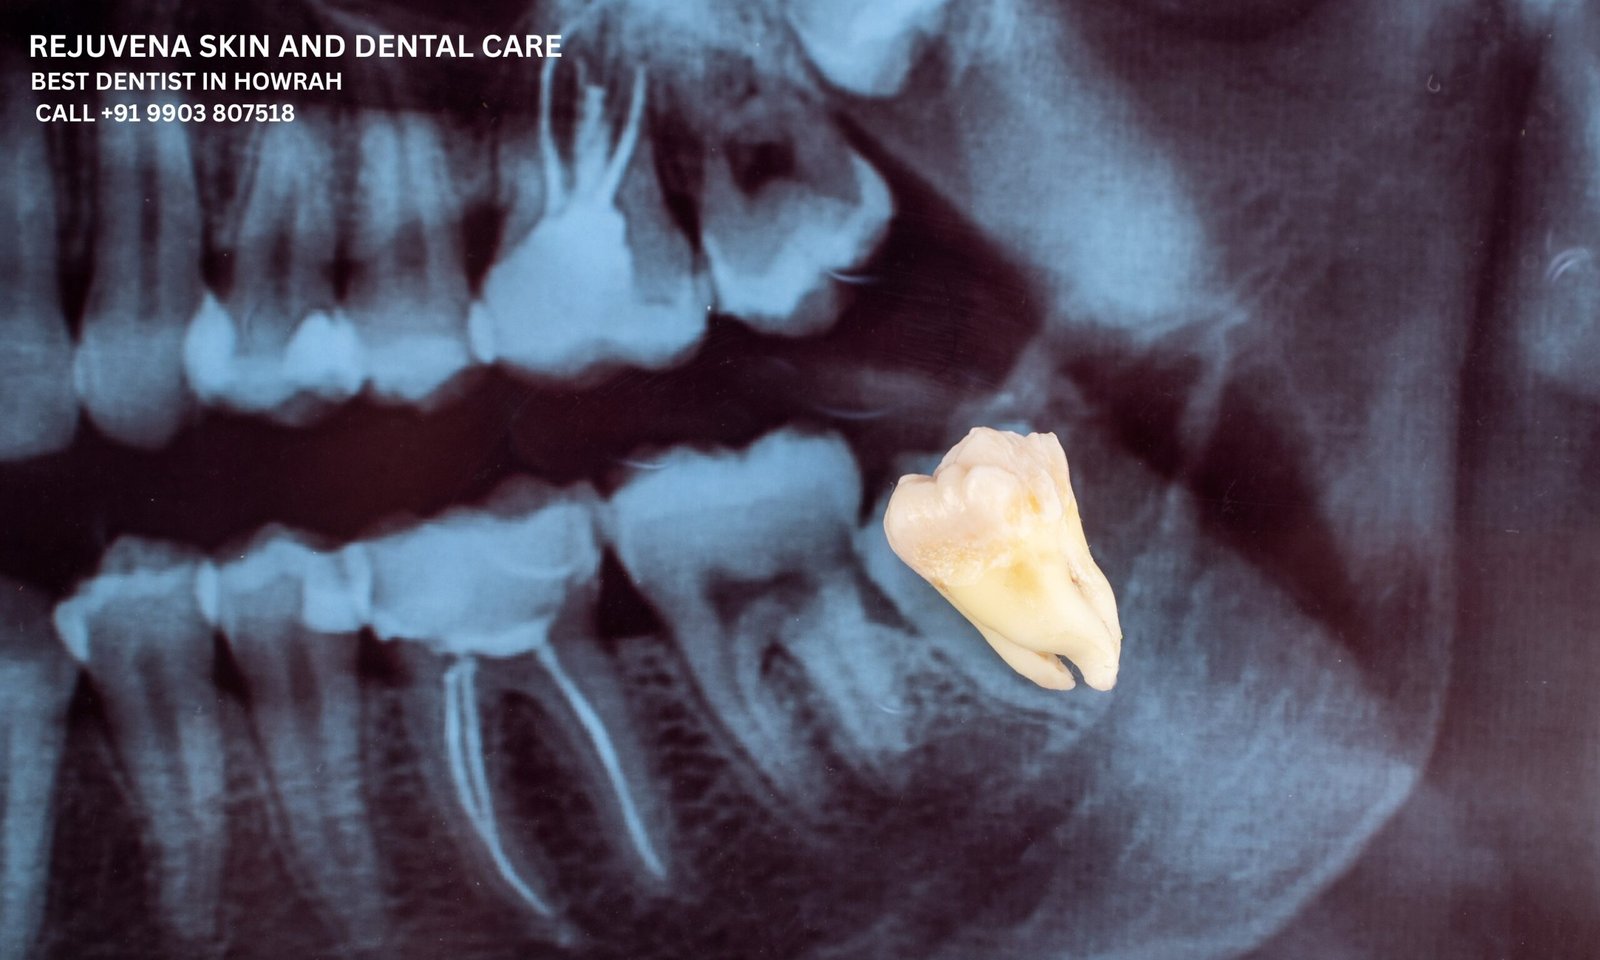

Surgical extraction is needed when a tooth is impacted, broken below the gum line, or requires gum or bone removal for access. Our skilled oral surgeons at Rejuvena use minimally invasive techniques for surgical extractions, including impacted wisdom teeth and fractured roots. We prioritize patient safety, comfort, and speedy recovery. If you’re seeking surgical dental extraction in Howrah or oral surgery near B Garden, trust the Rejuvena team for expert care backed by modern equipment and surgical precision.